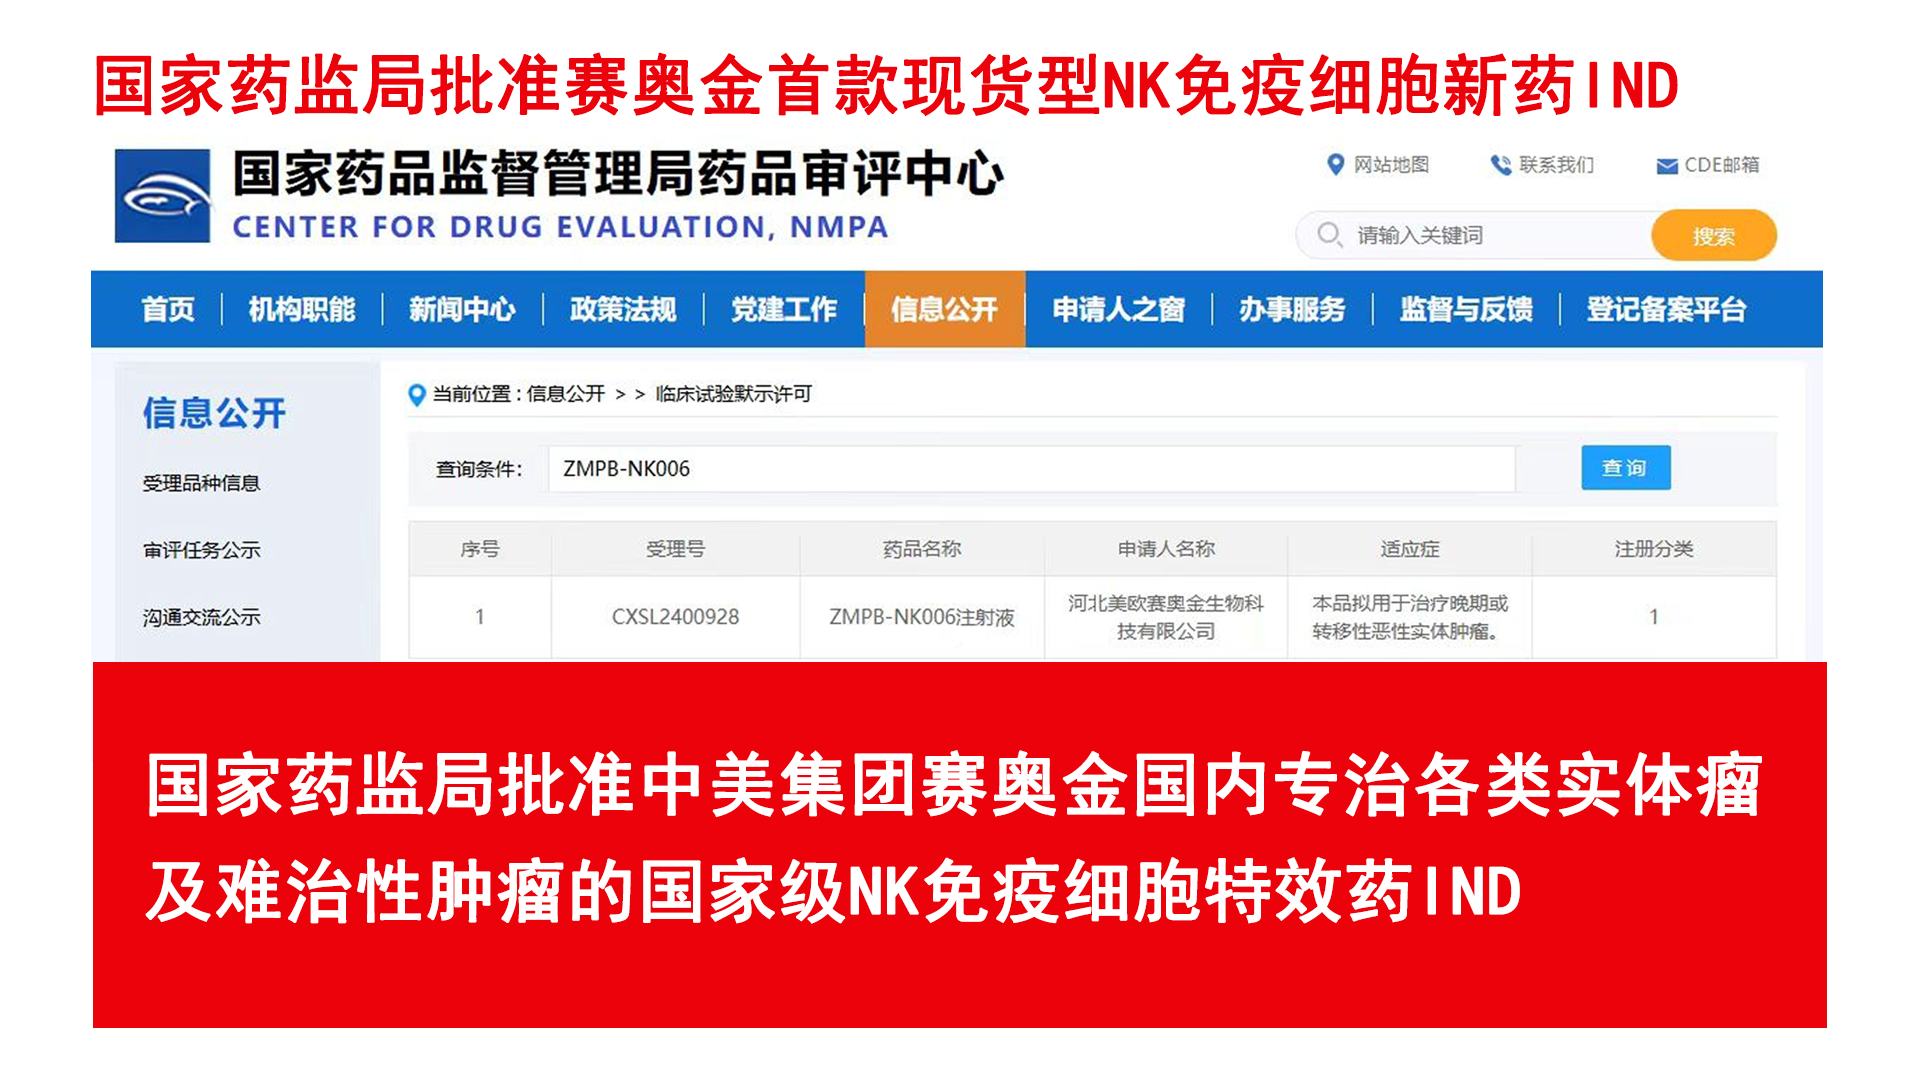

深圳赛奥金生物科技有限公司是美国赛奥金、中美赛奥金集团旗下核心企业,依托集团30余年行业积淀强势落址深圳前海自贸试验区核心区域。公司业务版图涵盖医疗连锁、细胞生物、生物制药、高等教育、公益慈善五大领域,以美国洛杉矶总部为技术支撑,深度整合中美跨境细胞治疗技术与资源,致力于成为中美细胞治疗协同创新与资源整合的核心枢纽。

以全球领先的免疫细胞技术,为晚期实体瘤患者提供普惠、可及的突破性治疗方案,推动细胞治疗产业的创新与发展。

成为立足中国、协同全球,引领下一代细胞治疗技术的创新型企业,为全球肿瘤治疗贡献中国智慧与解决方案。

国际领先六大肿瘤疗愈体系,确保每一位肿瘤患者得到超越预期的肿瘤疗愈,康复,终身健康保障服务。中美国际肿瘤连锁:郑州誉美肿瘤医院,武汉名逸肿瘤医院、博鳌华侨肿瘤医院。